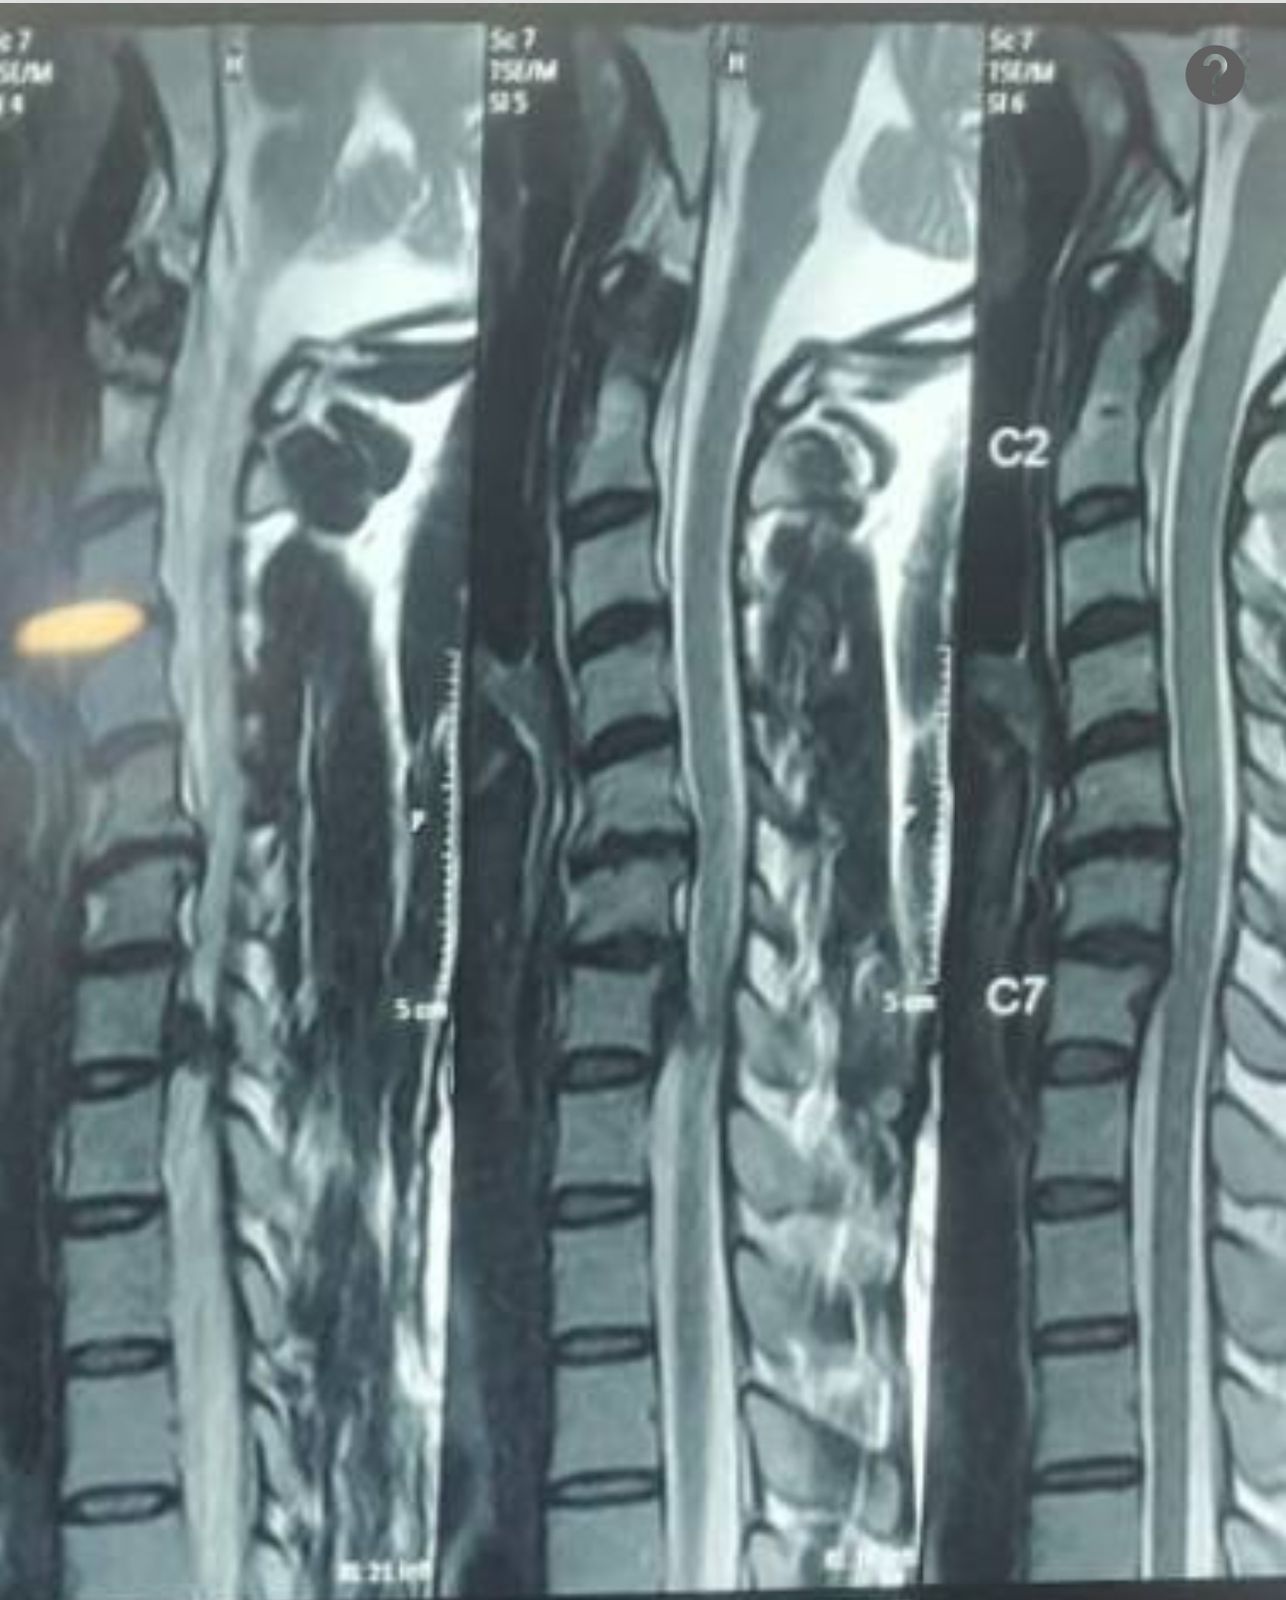

- Intramedullary Tumors begin in the cells within the spinal cord itself, such as gliomas, astrocytoma or ependymomas.

- Extramedullary Tumors grow in either the membrane surrounding the spinal cord or the nerve roots that reach out from the spinal cord. Although they don’t begin within the spinal cord itself, these types of tumors may affect spinal cord function by causing spinal cord compression and other problems. Examples of extramedullary tumors that can affect the spinal cord include meningiomas, neurofibromas, schwannomas and nerve sheath tumors.